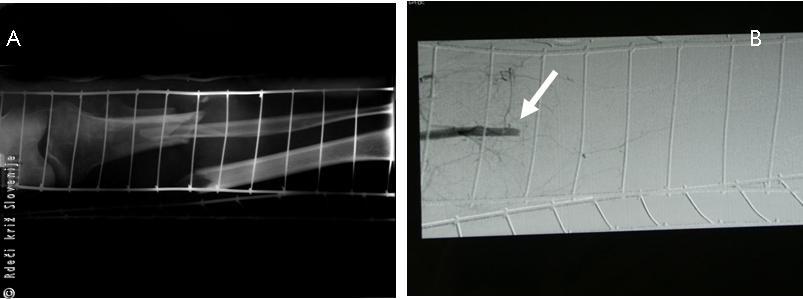

Kontrastna preiskava žilja (angiografija) je pokazala, da se od desne kolenske špranje ne prikaže nobena arterija. Z rentgensko preiskavo so ugotovili zdrobljen zlom desne goleni.

Slika 29

A – RTG je pokazal zdrobljen zlom goleni s premikom kostnih odlomkov.

B – Kontrastna preiskava žilja je pokazala prekinitev polnjenja kontrasta (prekinitev prekrvitve v področju zloma) zaradi poškodbe arterije.